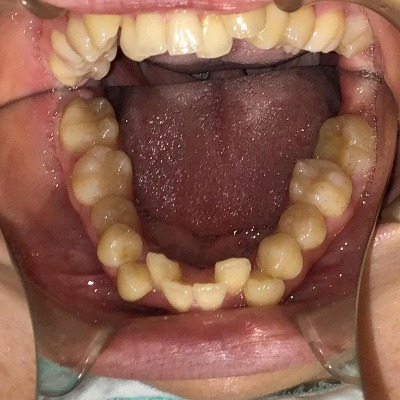

下顎

| 治療詳細 | 叢生や交叉咬合を整えるために、歯の表面にアタッチメント(白い突起)をつけ、IPR(歯と歯の間を削る)を行いました。 また、顎間ゴムと呼ばれる引っ掛けるゴムの補助装置も用いて治療を行いました。 抜歯を1本して治療を行いました。該当部分は義歯を使用しています。 |

| 主訴 | 歯のがたつき 一部分だけかみ合わせが反対 |